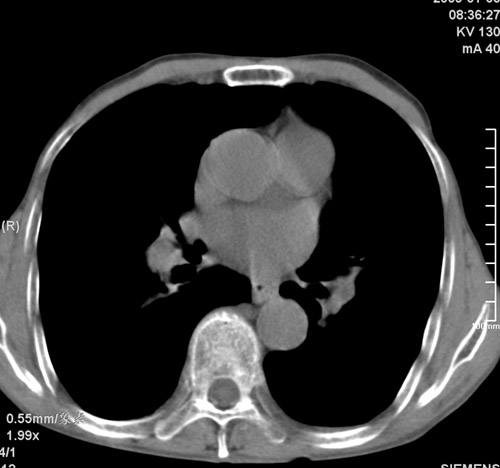

标题: CT17529:男 76 胸背部不适半月 胸透支气管炎 行CT检查 [打印本页]

标题: CT17529:男 76 胸背部不适半月 胸透支气管炎 行CT检查

意见 老年肺 少许炎症 肺大泡 右肺门略大 但支气管通畅  请各位高手指教如何下意见

支持楼主意见,右肺门略大,可能为肺动脉增粗.

慢支肺气肿,肺动脉高压.